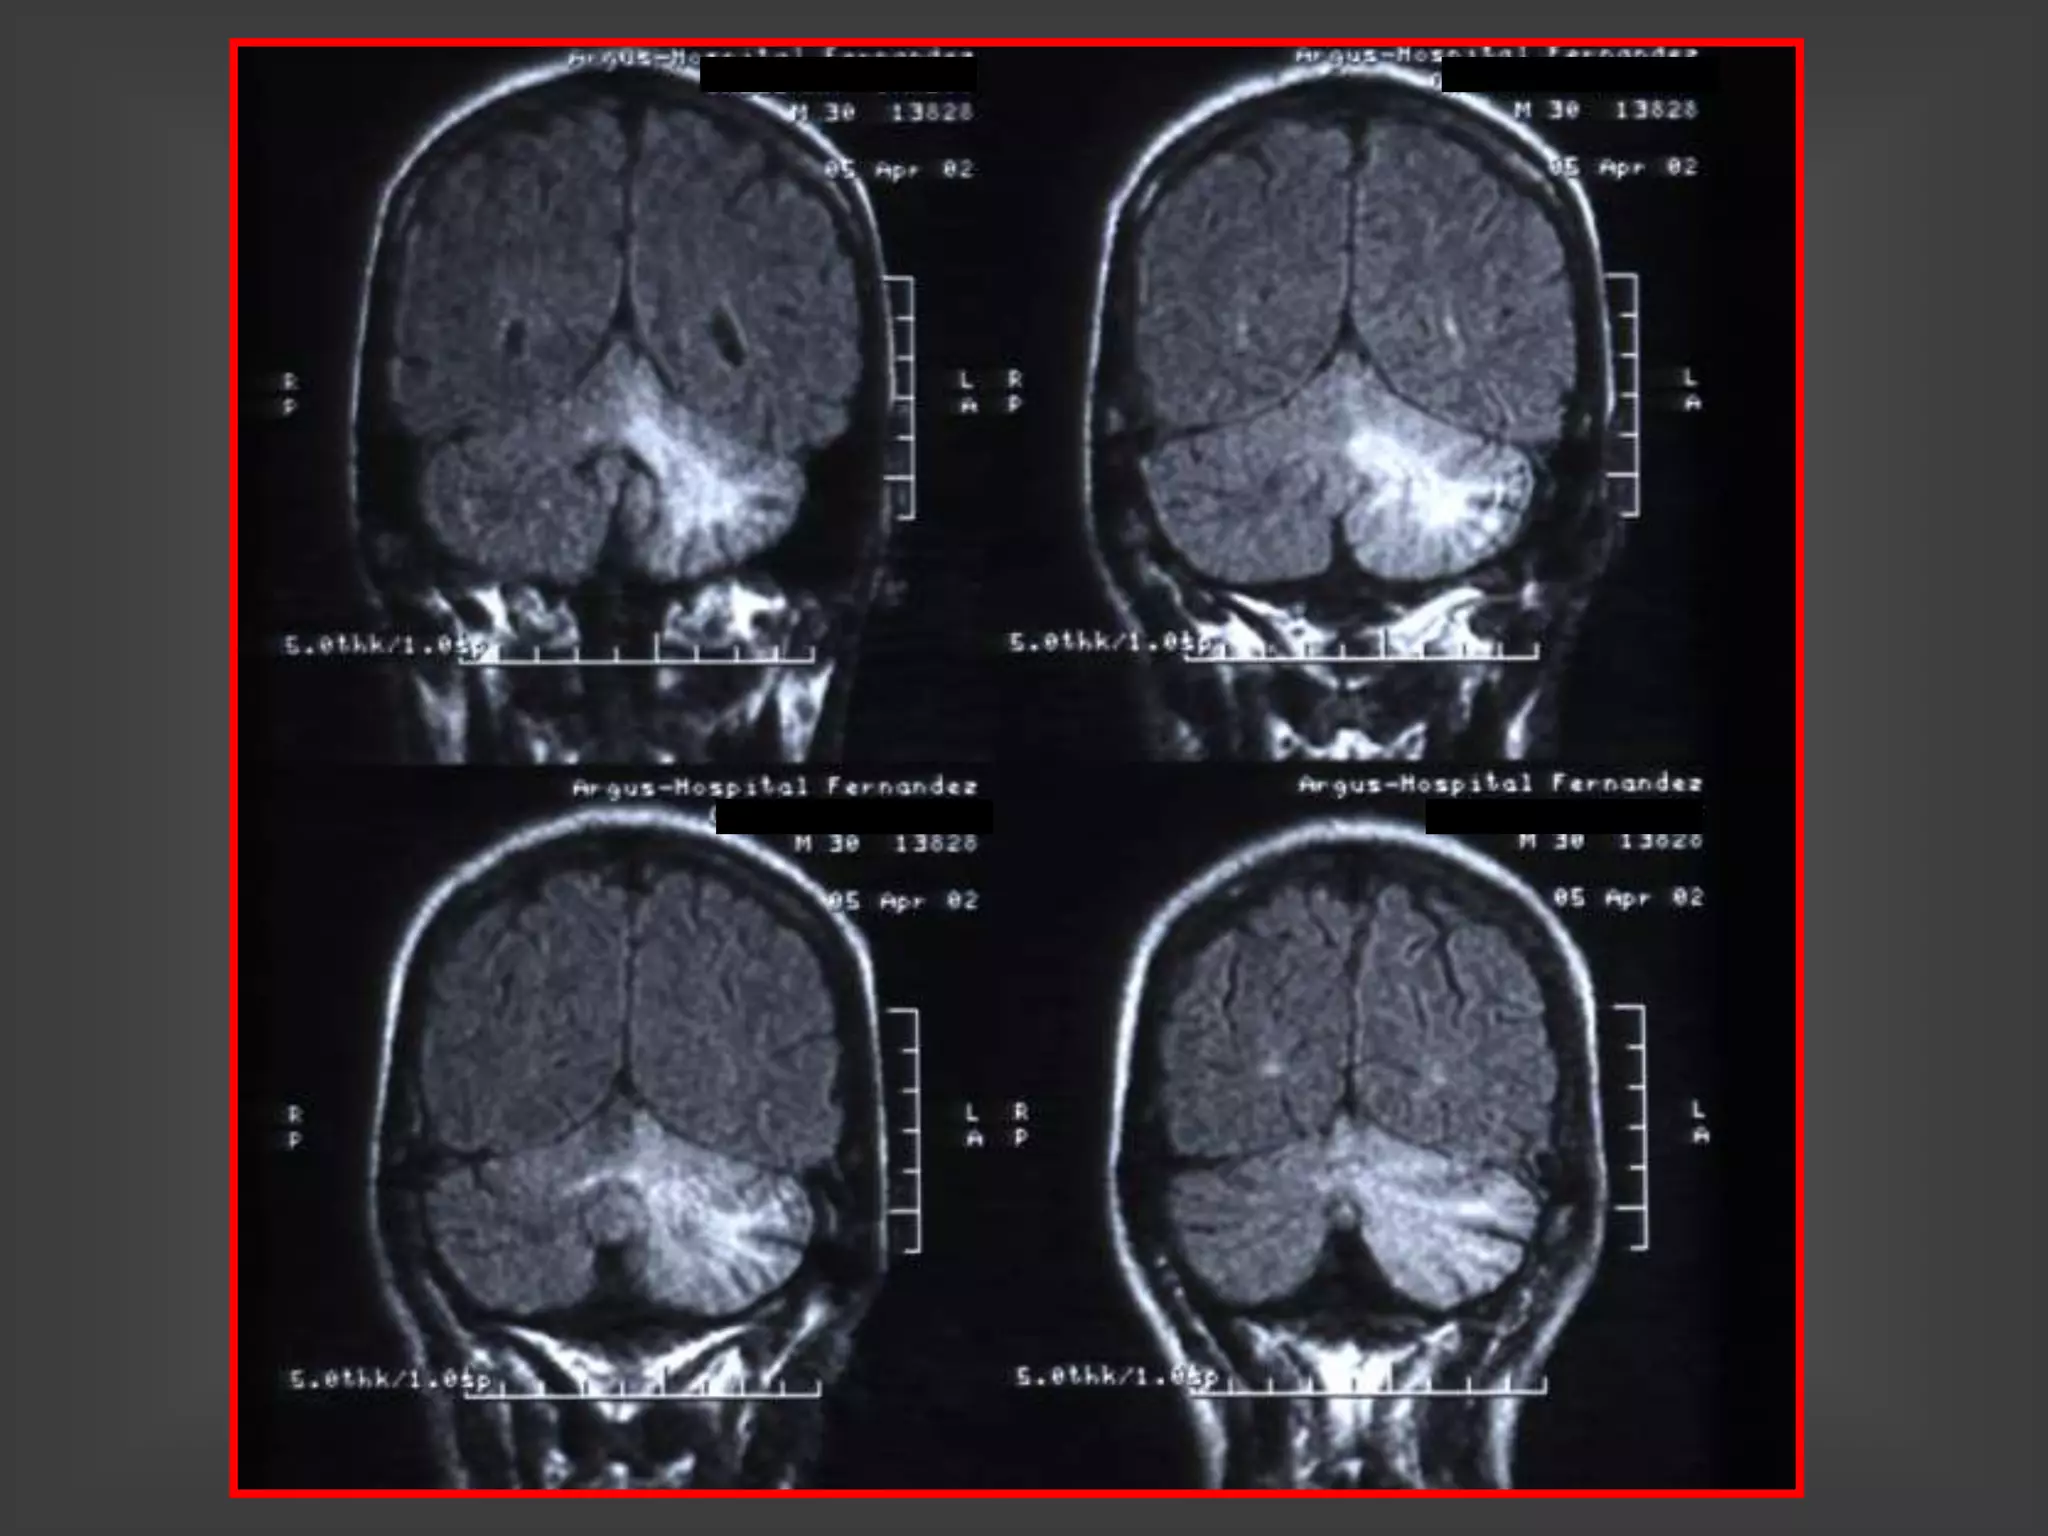

CHAGOMA - ESPECTROSCOPIA

CHAGOMA CEREBRAL

ESPECTROSCOPIA

CHAGOMA DE CUERPO CALLOSO

CHAGOMAS CEREBRALES

ENFERMEDAD DE CHAGAS

y SIDA

ABSCESOS CEREBRALES FOCALES

MENINGOENCEFALITIS DIFUSA

AMASTIGOTES EN BIOPSIA

CEREBRAL

TRIPOMASTIGOTES EN LCR